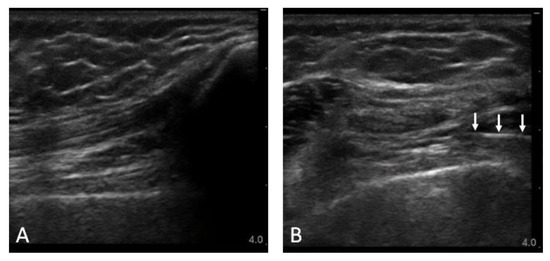

3.3. Ultrasound Examination